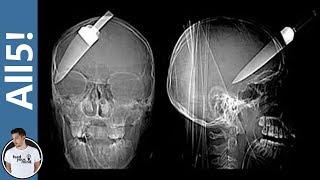

5 Strangest Things Found In X-Rays!